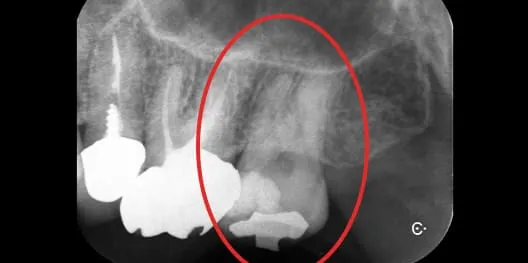

歯科用CTで根管の状態を

精密に診査・診断

01根管は一本一本形が異なり、湾曲や分岐が存在することもあります。歯科用CTを用いることで、従来の二次元レントゲンでは把握しにくい根の本数や方向、骨の状態まで立体的に確認できます。事前に正確な診査・診断を行うことで、治療計画の精度が高まり、無理のない安全なアプローチが可能です。見えない部分を「想像」ではなく「確認」することが、成功率向上の鍵となります。